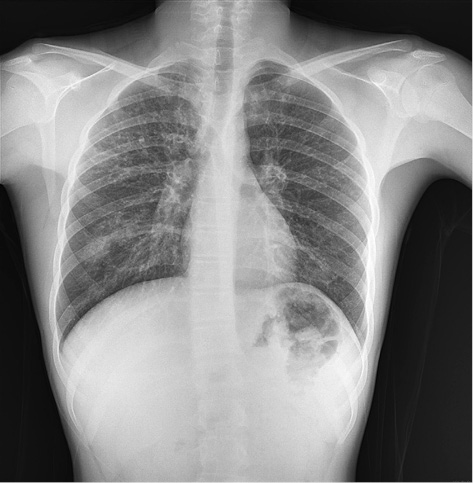

Figure 1. Bilaterally interstitial reticular densities and tram-tract appearance due to bronchiectasis in X-ray graph

In the systemic examination, bilaterally rales were present in lung auscultation. The peripheral pulses were normal. S1 and S2 were rhythmic, with no murmur, in normal sinus rhythm. In the laboratory, the neurological examination was normal. In X-ray chest graph, bilaterally tram-track linear opacities were observed [Figure 1]. These signs were interpreted as bronchiectasis due to CF. The patient had defences and rebound in the abdominal examination. WBC was 14,000×109/L. In the USG, the appendix was distended and no taken response to compression. He was operated on with a preliminary diagnosis of acute appendicitis. Unfortunately, since this rare diagnosis of the patient was not predicted, no images were obtained during the operation and sonographically.